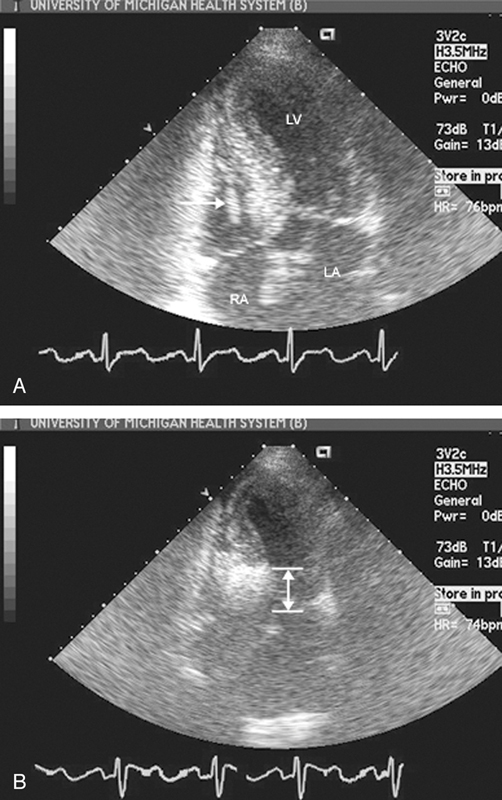

فحوصات تشخيصية لبعض امراض القلب والشرايين التاجية